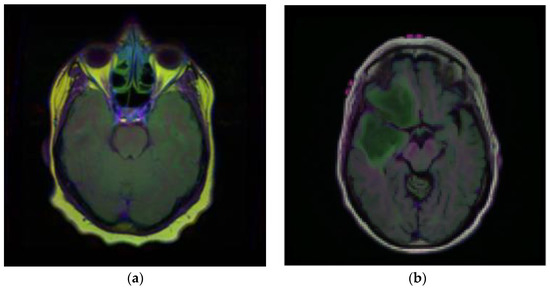

Brain MRI scans from 110 patients with 3929 brain MRI images are included in the dataset using FLAIR abnormalities. Out of the total 3929 dataset images, 90% of the data are used for training and 10% are used for testing. After that, out of the 90% training data, 15% are used for the validation set. Figure 2 illustrates the brain MRI images taken from Kaggle [28,29]. Figure 2a displays the normal image and Figure 2b displays the tumor image of the brain in which two tumor regions are shown with a break in between. It is difficult to segment this break region in the tumor part. The proposed methodology shown in Figure 3 is also segmenting this break part accurately.

Figure 2.

Samples of Brain MRI Images (a) Normal Image, (b) Tumor Image.